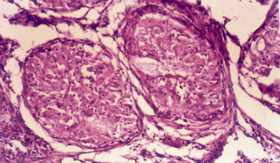

On examination, he had a confluent, non-blanching, macular, erythematous rash on both palms (Box 1), but no other skin rash elsewhere on the body. There was no thyromegaly or peripheral lymphadenopathy, and there were no abdominal, cardiovascular, respiratory or nervous system abnormalities. Ophthalmological examination was suggestive of episcleritis.

A Mantoux test was non-reactive. The serum level of angiotensin-converting enzyme was 76.2 U/L (normal range, 8–52 U/L). A skin biopsy taken from the palmar rash revealed non-caseating granulomas with multinucleated giant cells (Box 1). No acid-fast bacilli or fungal hyphae were detected on direct staining or subsequent culture of sputum and skin biopsy specimens. The histological features were thus suggestive of sarcoidosis.